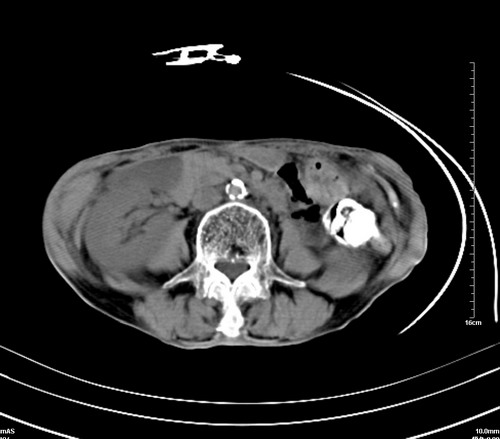

病人,女,79岁,主要因腹疼二月入院,彩超,肝,胆,脾,未见异常,胸透上消化道造影未见异常,化验白细胞增高,内科医生让做胸部ct检查,因为熟人多做了腹部(外科会诊考虑胆囊炎).现ct片如下请假各位战友.

1 气管旁、隆突下淋巴结明显肿大,肝左叶外侧段低密影,都考虑转移。

2 肝右后叶下段明显增大,片状低密影,但因各种伪影显示不佳,不排除病变。

后中纵隔团块影,伴气管、食道受压移位,首先考虑转移瘤,肝s5段低密度灶。建议增强检查,另外其结肠是否有问题请提供,右肺部分肺叶局限含气增多,考虑局限肺气肿。

后中纵隔团块影,伴气管、食道受压移位,首先考虑转移瘤,肝表现同11773。